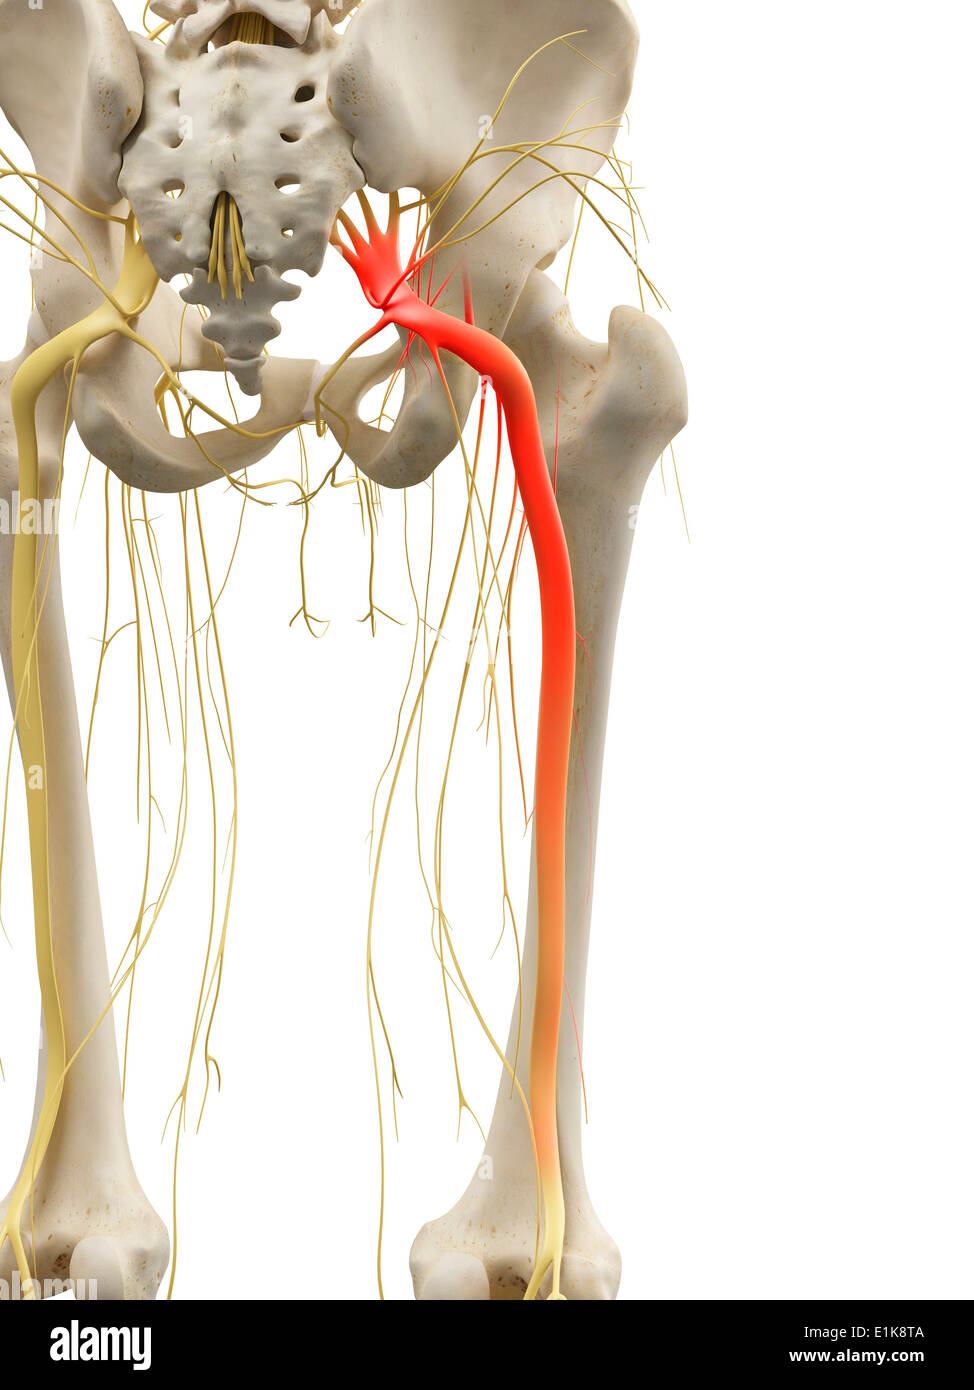

Nerf sciatique de l'art de l'ordinateur. Banque D'Imageshttps://www.alamyimages.fr/image-license-details/?v=1https://www.alamyimages.fr/nerf-sciatique-de-l-art-de-l-ordinateur-image69880170.html

Nerf sciatique de l'art de l'ordinateur. Banque D'Imageshttps://www.alamyimages.fr/image-license-details/?v=1https://www.alamyimages.fr/nerf-sciatique-de-l-art-de-l-ordinateur-image69880170.htmlRFE1K8TA–Nerf sciatique de l'art de l'ordinateur.